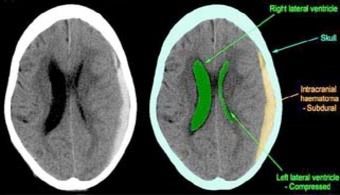

A chronic sub-dual haematoma is a brain disorder involving a collection of blood in the space between the inner membranes that cover the brain and the outer membrane covering of the brain, with symptoms occurring two weeks or more after the injury that caused the leak of blood. |

Chronic subdural haematomas are caused by injuries to the head. The head injury could be as minor as a bump, or as serious as a car accident. The blood slowly collects and presses on the brain tissue, which in turn can become inflamed. The growing leakage of blood, and inflammation can cause pressure on the brain, causing a gradual loss of brain function.